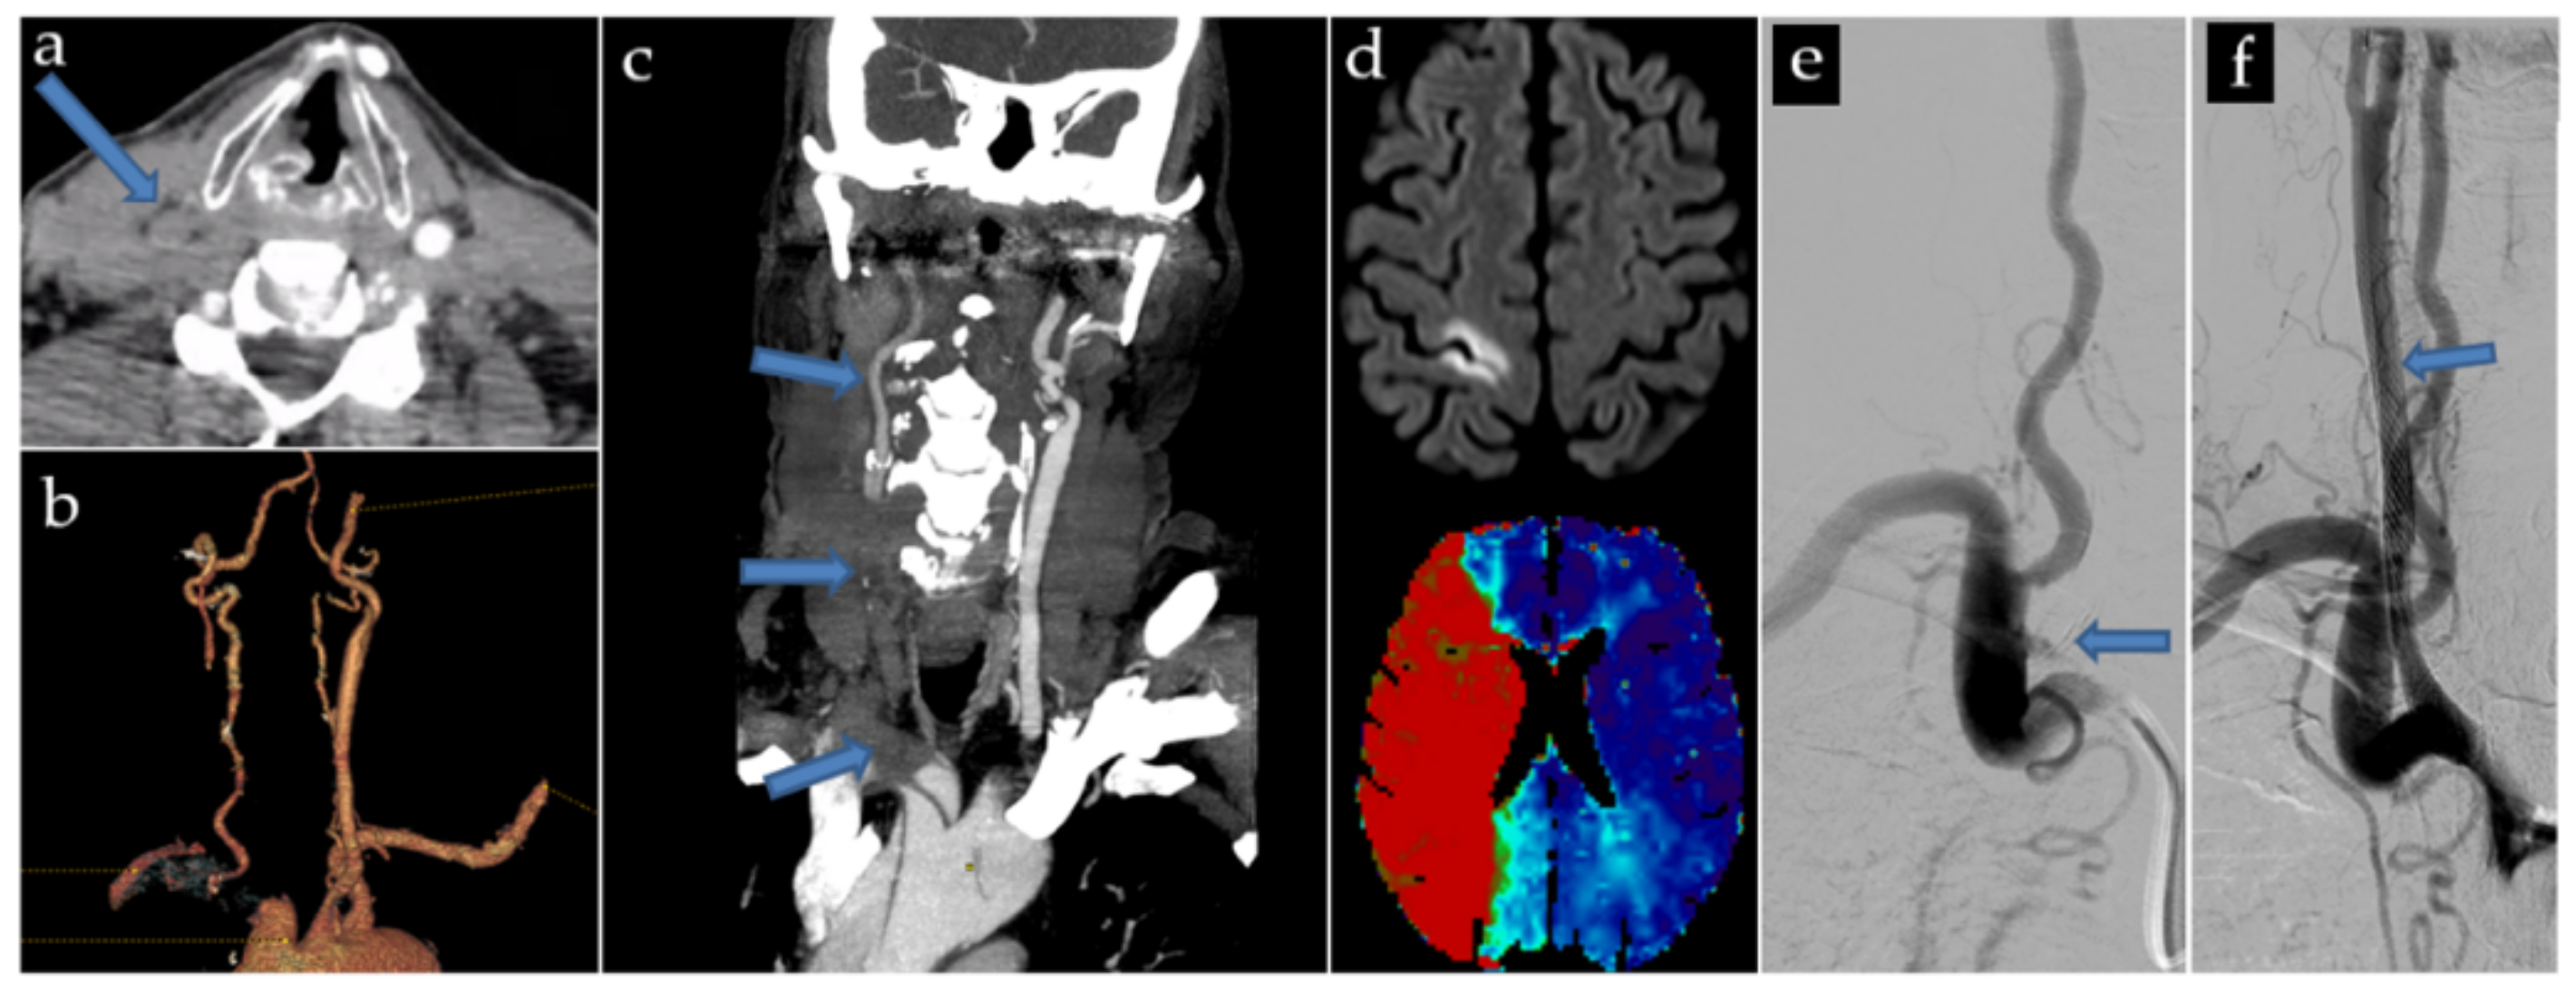

- A 78 yo patient presented with a distal A2 embolus, too distant to be accessible by thrombectomy. Three 9 × 30 mm Carotid Wallstents were used, covering the entirety of the brachiocephalic trunk and right common carotid artery. After deployment of the first two Carotid Wallstents, an intra-stent thrombosis occurred, and was immediately and successfully treated by aspiration, and was not recurrent. Antiplatelet treatment was started the next day.

- A 74 yo patient presented a sylvian M2 embolus at the end of the procedure, successfully treated by thrombectomy immediately after stenting with three Carotid Wallstent (7 × 40 mm, 9 × 50 mm and 5 × 30 mm) and a Smart Control 14 × 40 mm. Antiplatelet treatment and preventive low molecular weight Heparin were started the next day.

- A 62 yo patient presented multiple distal emboli not accessible to thrombectomy. Antiplatelet treatment and curative low molecular weight Heparin were started 12 h post-procedure.